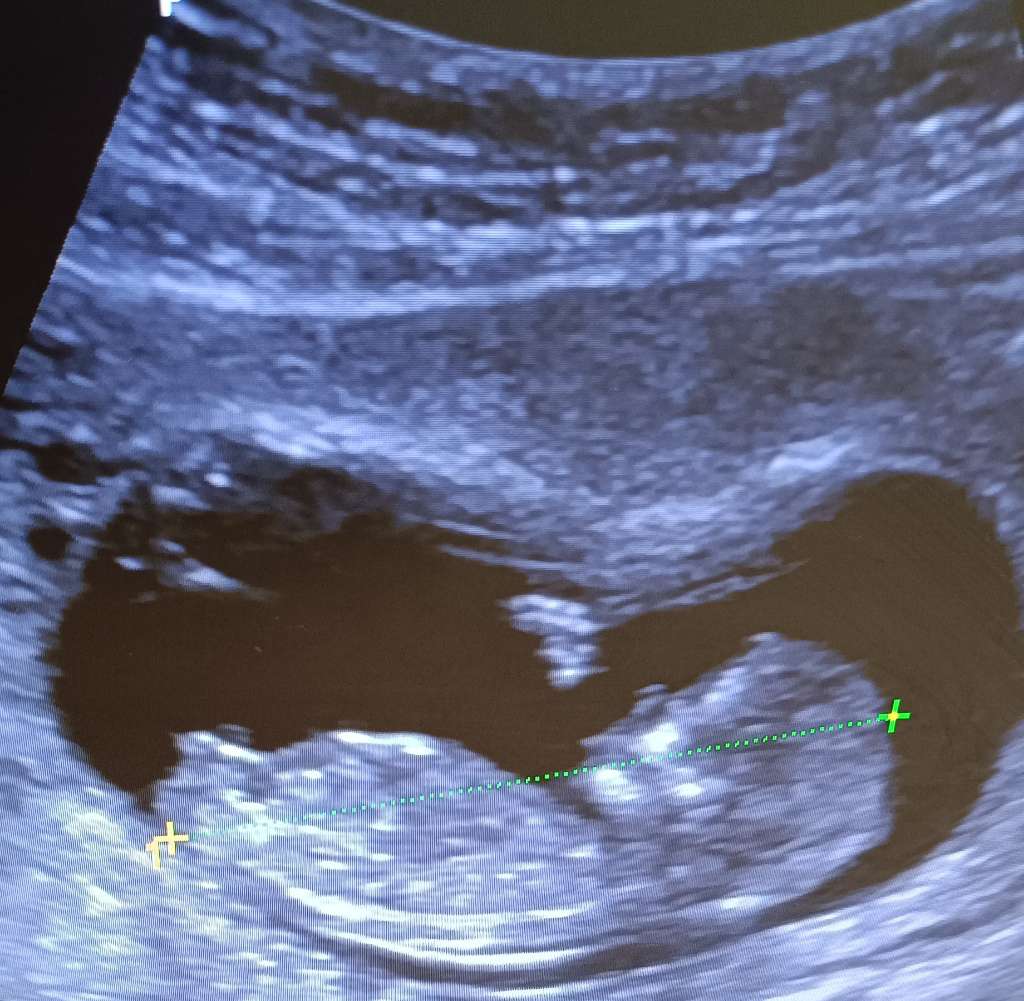

Moje zdjęcie z 12+5, lekarz był pewny że chłopiec i się potwierdziło 🙂

11,4 KB · Wyświetleń: 111